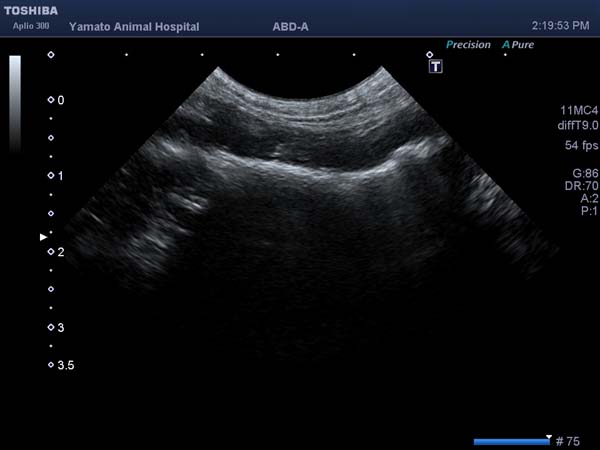

ひも状の異物を飲み込んだワンちゃんが腸閉塞の症状で来院されました。超音波検査では小腸の遠位にひも状異物による閉塞症状が確認されました。開腹すると空腸に異物が確認されました。指で優しく逆行性に胃まで異物を押し戻し内視鏡にて摘出しました。この方法では胃を通り過ぎてしまった異物でも、異物の形状によっては消化管切開をせずに取り出せますので、術後の回復も早く動物にやさしい手術となります。今回のワンちゃんも早期に元気に退院できました。良かったね。